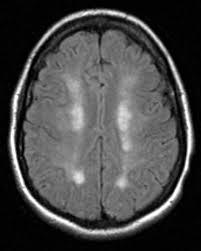

45 y/o woman with hypertension is resuscitated after a cardiac arrest. On day three she is not moving her limbs. An MRI looks like this.

There are multiple areas of watershed in the brain

MCA is most affected in global hypotension

Posterior circulation is rarer